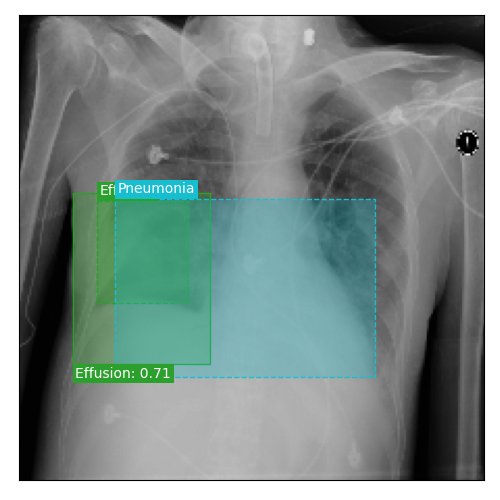

Qualitative Results

As shown in Fig. 4 Loc-ADPD detects cardiomegaly almost perfectly, as it is always exactly localized at one anatomical region. Other pathologies are detected but often with too large or too small boxes as they only cover parts of anatomical regions or stretch over several of them, which cannot be completely corrected using WBF. Detection also works well for predicting several overlapping pathologies. For qualitative comparisons between Loc-ADPD and MIL-ADPD, we refer to Appendix 0.B.

Appendix 0.B Qualitative Results and Failure Cases

| Loc-ADPD | MIL-ADPD | Loc-ADPD | MIL-ADPD |

![]() |

| (a) | (b) | ||